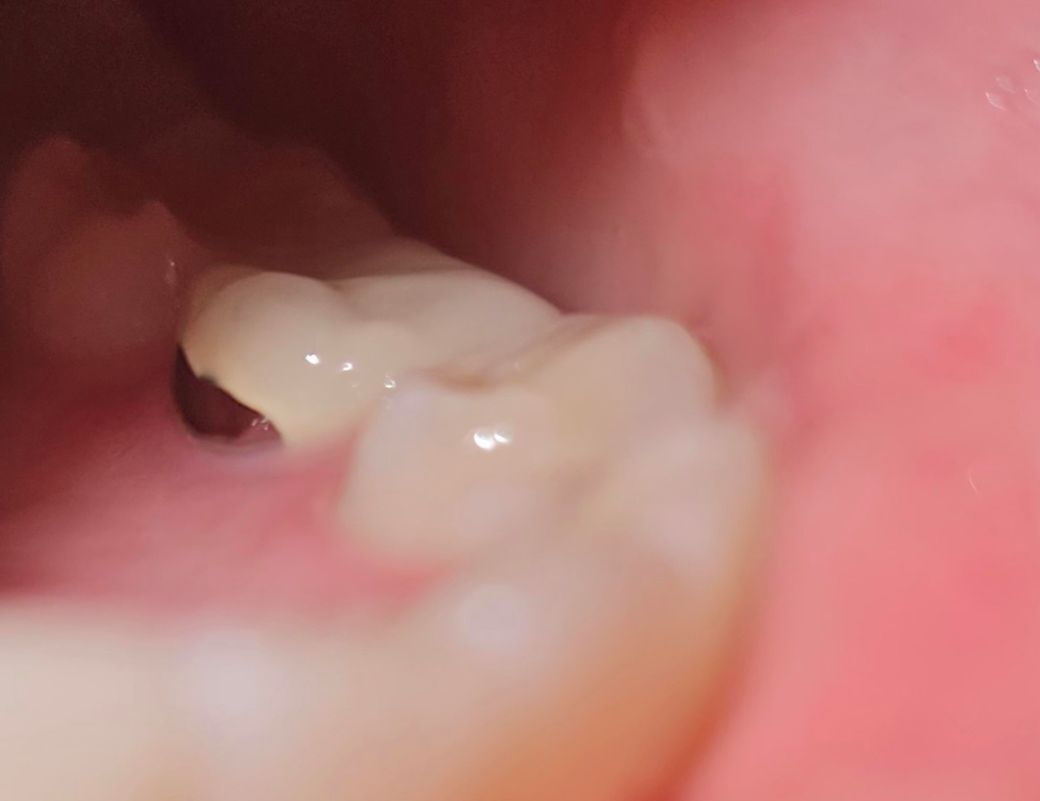

전에 씌웠던 크라운과 잇몸 사이 검은게 보이길래 후래쉬키고 찍어봤더니 사이에 구멍이 있는 것 같아요 며칠 전 치과 갔을 때는 의사선생님께서 언급 안 하셨어요 크라운이 깨진 걸까요?

혀로 해당부위 훑어보면 구멍이 아닐겁니다 pfm 크라운의 구조로 안쪽 안보이는쪽은 메탈이고, 바깥쪽은 치아색나는 포세린입니다

크라운의 재료가 메탈이 섞여있는 재료인 것으로 보입니다. 구멍이 있으면 혀로 날카롭게 만져집니다.

크라운의 도자기 부위와 금속부위 경계가 살짝 깨진거 같습니다. 큰 문제가 잇는건 아닙니다.

깨진것은 아니고 PFM(Porcelain Fused Metal) 이라는 보철물에서 metal 부위가 드러나보이는

것 입니다. 처음 만들때부터 저렇게 만들어져서 보이기 때문에 걱정하지 않으셔도 되겠습니다.